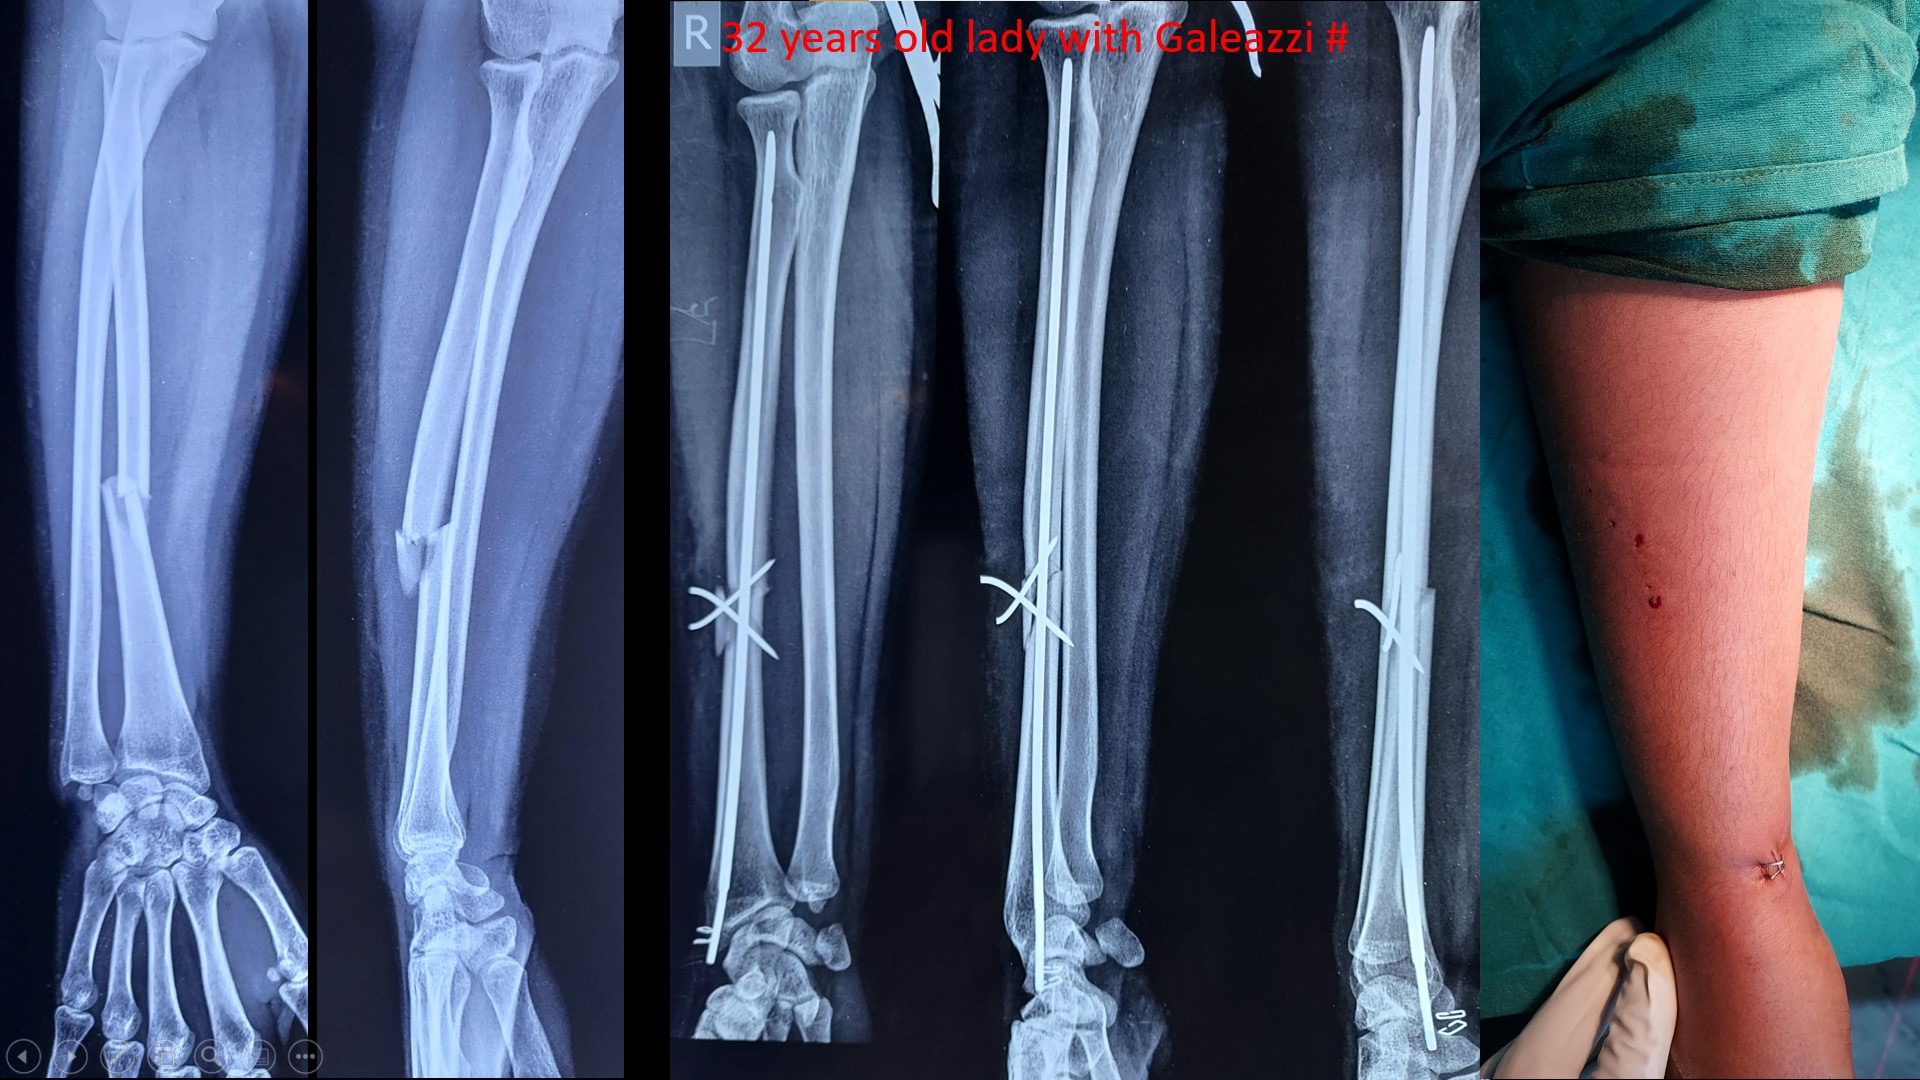

FOREARM FRACTURES